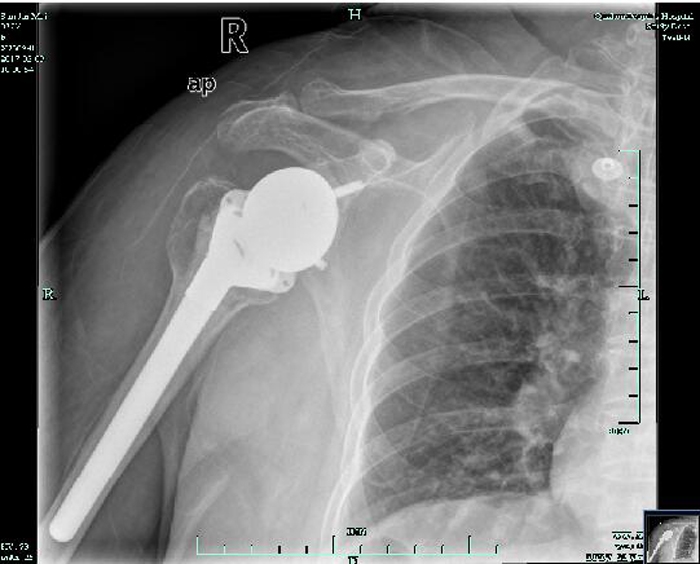

術(shù)后復(fù)查片

??? 經(jīng)過(guò)醫(yī)生的細(xì)致檢查,發(fā)現(xiàn)孫阿婆患有肱骨頭壞死、巨大肩袖損傷及肩關(guān)節(jié)骨性關(guān)節(jié)炎。5月7日,骨科運(yùn)動(dòng)醫(yī)學(xué)關(guān)節(jié)外科團(tuán)隊(duì)在何飛熊主任的帶領(lǐng)下,為孫阿婆成功實(shí)施了逆置型肩關(guān)節(jié)置換手術(shù)。

??? 該手術(shù)是我市開展逆置型肩關(guān)節(jié)置換手術(shù)的第一例。孫阿婆裝上的“假肩膀”,其實(shí)是用鈦合金等材料制成的肩關(guān)節(jié)假體,因?yàn)槭前仓迷诠穷^里的,所以從外觀上看不出來(lái),也不會(huì)給她的日常生活造成不便。